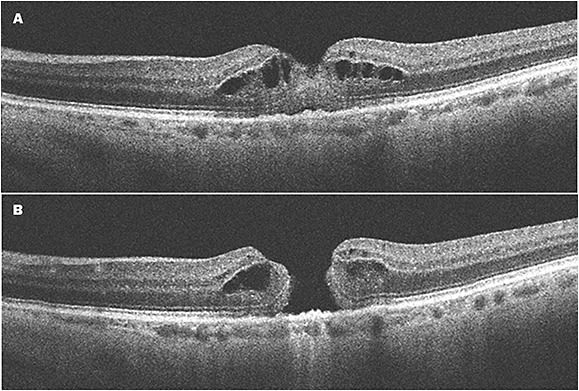

For instance: All OCT systems are equipped with an internal fixation target. When a patient with a full-thickness macular hole (or other pathology that produces a central scotoma) is directed to fixate on the target, the system will scan the patient’s subjective fixation. The resulting scan will be placed juxta-foveal, producing an image that does not reflect the pathology. A trained imager will recognize anatomical structures that indicate the patient is not fixating centrally and should adjust accordingly. In a busy clinical practice, this type of error may go unnoticed.